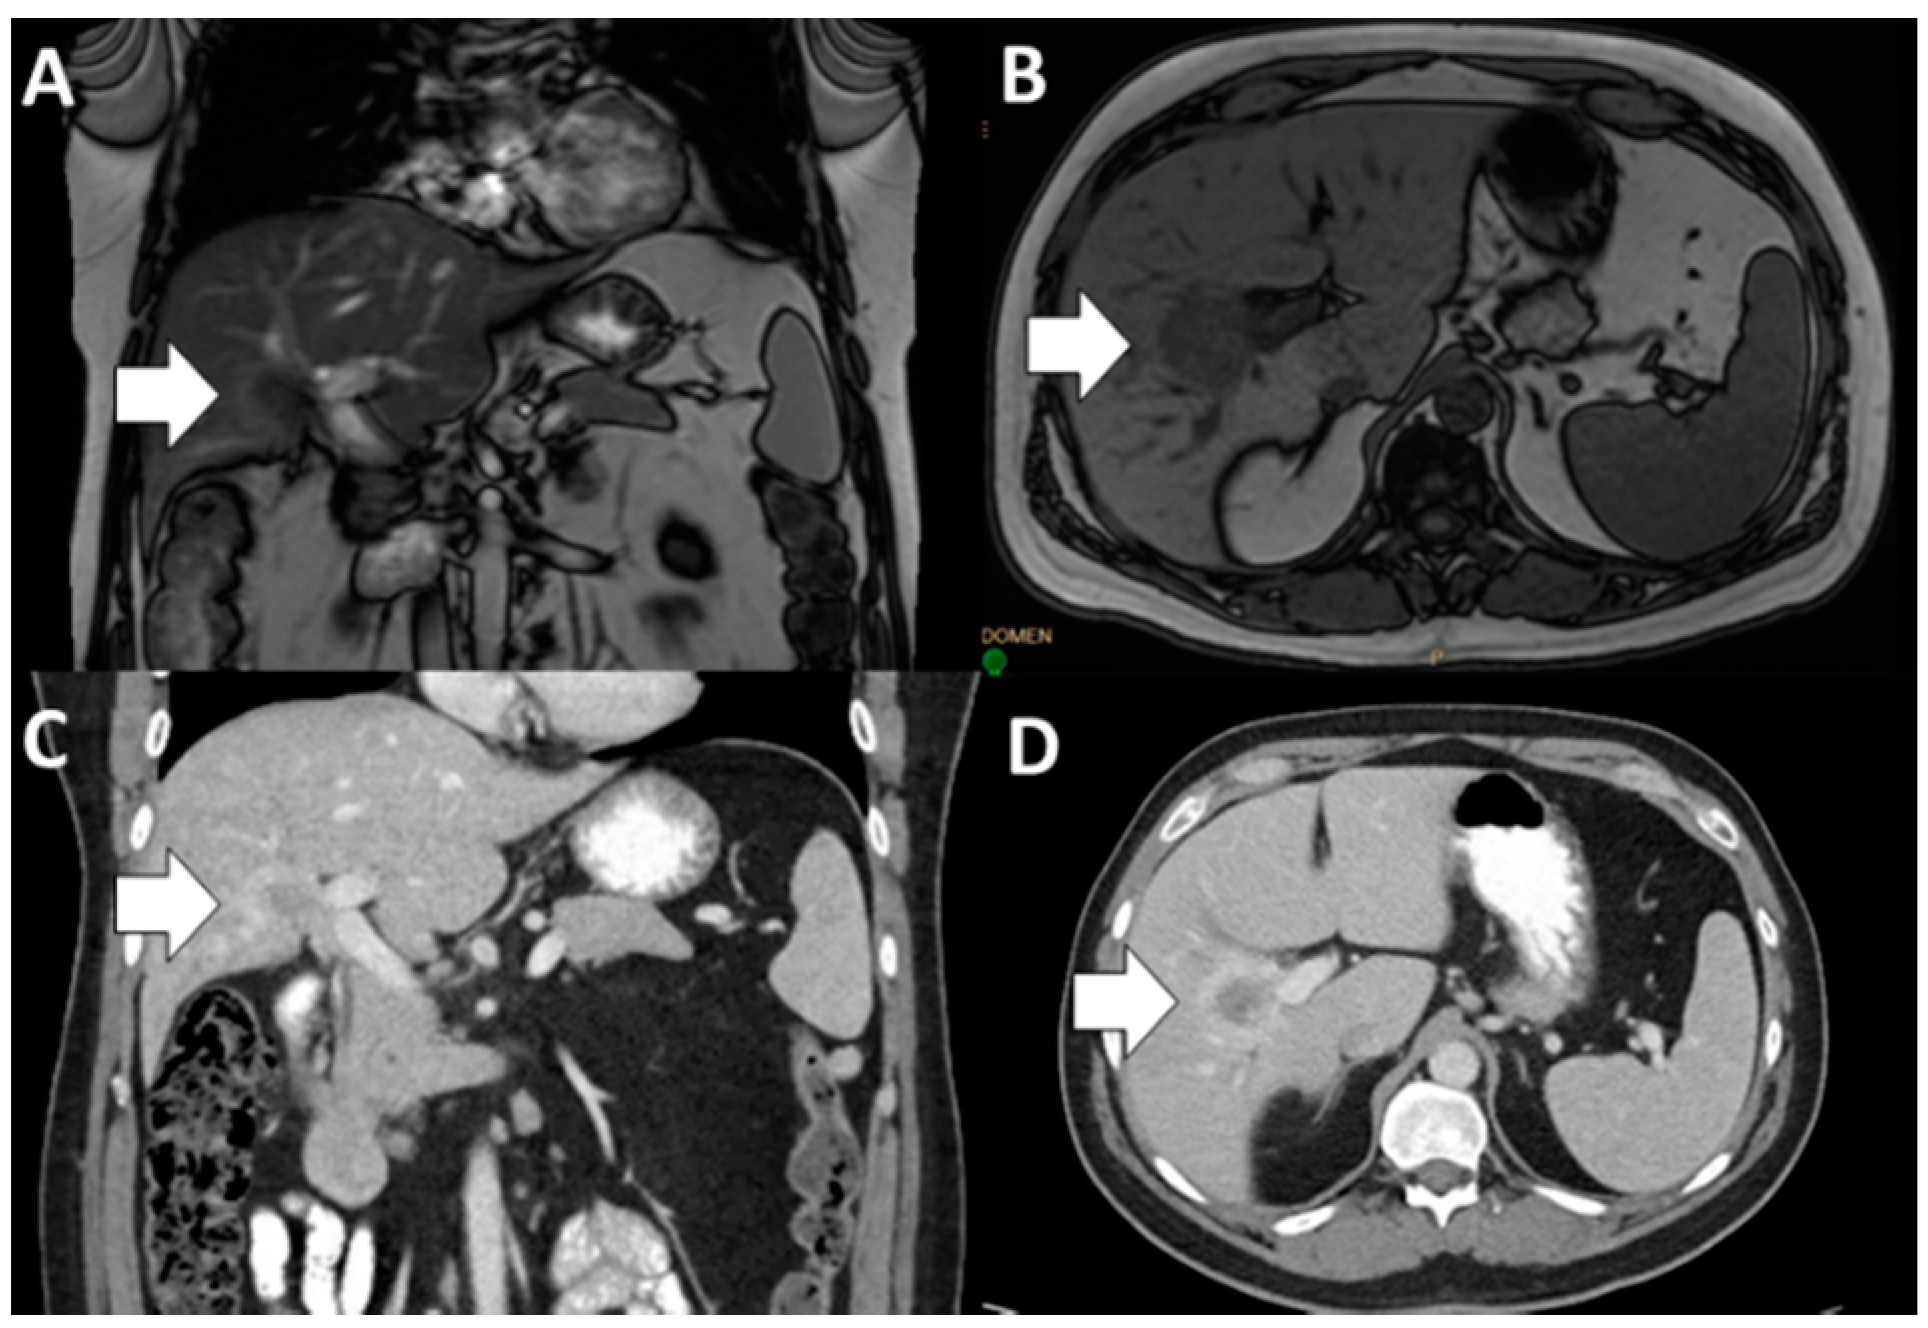

- Fábrega-Foster, K.; Ghasabeh, M.A.; Pawlik, T.M.; Kamel, I.R. Multimodality imaging of intrahepatic cholangiocarcinoma. HepatoBiliary Surg. Nutr. 2017, 6, 67–78. [Google Scholar] [CrossRef] [PubMed]

- Seo, N.; Kim, D.Y.; Choi, J.Y. Cross-sectional imaging of intrahepatic cholangiocarcinoma: Development, growth, spread, and prognosis. Am. J. Roentgenol. 2017, 209, W64–W75. [Google Scholar] [CrossRef]

- Itai, Y.; Ohtomo, K.; Kokubo, T.; Yamauchi, T.; Minami, M.; Yashiro, N.; Araki, T. CT of Hepatic Masses: Significance of Prolonged and Delayed Enhancement. Am. J. Roentgenol. 1986, 400, 729–733. [Google Scholar] [CrossRef]

- Yang, C.M.; Shu, J. Cholangiocarcinoma Evaluation via Imaging and Artificial Intelligence. Oncology 2020, 98, 1–12. [Google Scholar] [CrossRef]

- Kim, R.; Lee, J.M.; Shin, C.I.; Lee, E.S.; Yoon, J.H.; Joo, I.; Kim, S.H.; Hwang, I.; Han, J.K.; Choi, B.I. Differentiation of intrahepatic mass-forming cholangiocarcinoma from hepatocellular carcinoma on gadoxetic acid-enhanced liver MR imaging. Eur. Radiol. 2016, 26, 1808–1817. [Google Scholar] [CrossRef]